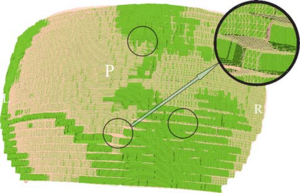

Publication: J Thorac Imaging. 2016 Jan;31(1):29-36. PMID: 26429588| PDF Authors: Zach JA, Williams A, Jou SS, Yagihashi K, Everett D, Hokanson JE, Stinson D, Lynch DA, COPDGene Investigators. Institution: Divisions of Radiology, Biostatistics and Bioinformatics, National Jewish Health, Denver, CO, USA. Background/Purpose: The purposes of this study were to evaluate the effect of smoking status on quantitative computed tomography CT measures of low-attenuation areas (LAAs) on inspiratory and expiratory CT and to provide a method of adjusting for this effect. Materials and Methods: A total of 6762 current and former smokers underwent spirometry and volumetric inspiratory and expiratory CT. Quantitative CT analysis was completed using open-source 3D Slicer software. Funding:

Examples of CN on CT. Coronal CT image of a GOLD 1 subject with moderately extensive visual extent of emphysema. However, the quantitative emphysema score was only 5.1%. The emphysema may have been masked on quantitative assessment by the presence of centrilobular nodules (circled) and patchy ground-glass abnormality (arrows). |